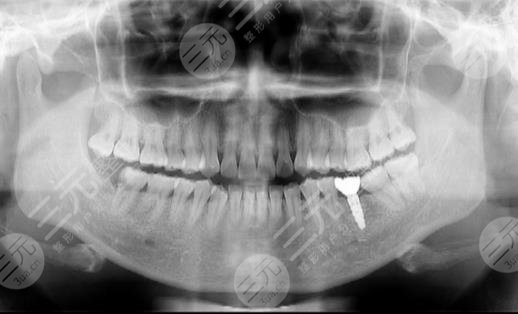

种植牙手术结束后的第一天,自己的口腔状态要比以前完整和完善了,这种种植体能够很好的填充在自己的牙槽骨里面,没有出现剧烈的疼痛感,同时也没有出现较为严重的挤压现象。在装了牙冠后的第七十七天,感觉自己的口腔变得更加的精美了,整个人的颜值也得到了很好的提升,笑起来较为的甜美,每一颗牙齿的形态都特别的正常,没有出现虫牙了,也没有了孔洞。

做完缓解后的第两百八十八天,自己的口腔状态依然较为的美观,每一颗种植体和以前的牙齿颜色其实是差不多的,看上去没有较为异常的感觉。